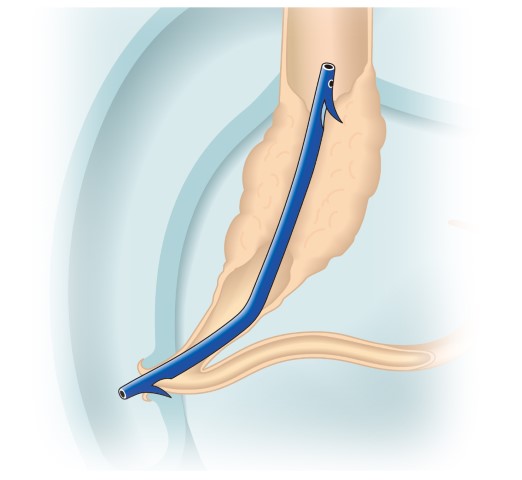

数年前まで小腸の内部を直接観察することは困難であり、小腸疾患が疑われても容易には診断を下せないケースが多くありました。ところが最近では内視鏡技術の進歩によって全小腸内視鏡観察が可能となり、今後は小腸内視鏡検査の必要性が増々高くなっていくと考えられます。

シングルバルーン式小腸内視鏡 |

イメージ |

|

| (画像提供:オリンパス株式会社) | ||